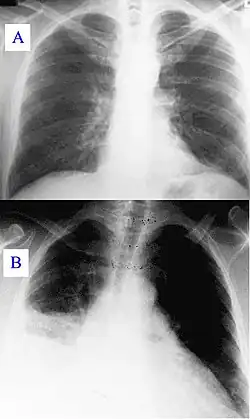

New or progressive infiltrate on the chest X-ray with one of the following:[3]

In hospitalised patients who develop respiratory symptoms and fever, one should consider the diagnosis. The likelihood increases when upon investigation symptoms are found of respiratory insufficiency, purulent secretions, newly developed infiltrate on the chest X-Ray, and increasing leucocyte count. If pneumonia is suspected material from sputum or tracheal aspirates are sent to the microbiology department for cultures. In case of pleural effusion, thoracentesis is performed for examination of pleural fluid. In suspected ventilator-associated pneumonia it has been suggested that bronchoscopy or bronchoalveolar lavage is necessary because of the risks of incorrect clinical diagnoses.[1][3]